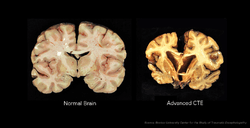

The primary physical manifestations of CTE include a reduction in brain weight, associated with atrophy of the frontal and temporal cortices and medial temporal lobe. The lateral ventricles and the third ventricle are often enlarged, with rare instances of dilation of the fourth ventricle.[6] Other physical manifestations of CTE include anterior cavum septi pellucidi and posterior fenestrations, pallor of the substantia nigra and locus ceruleus, and atrophy of the olfactory bulbs, thalamus, mammillary bodies, brainstem and cerebellum.[7] As CTE progresses, there may be marked atrophy of the hippocampus, entorhinal cortex, and amygdala.[2]